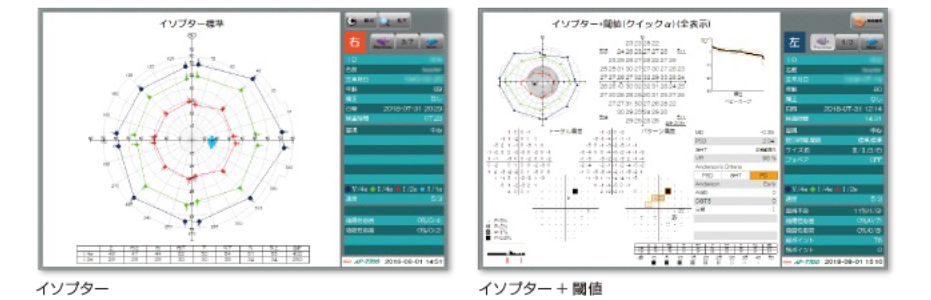

コーワ AP-7700

・動的視野検査も実施でき周辺視野と中心視野の同時評価が可能です。

医師が時系列で症状を分析することにより治療方針が立てやすく、患者様にも診察においてひとめで症状が伝わりやすいです。